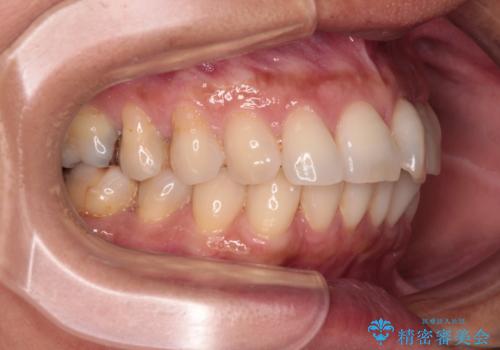

むし歯と前歯のデコボコを治したい インビザラインを使用した総合歯科治療

- 目立つ銀歯やむし歯、前歯のデコボコを気にして来院された患者様です。

デコボコはある程度改善できれば良いとのことでしたので、インビザラインの廉価版を用いて矯正治療を行うこととしました。

飛行機での通院であり、更にはご家族がの都合で海外に滞在されることも多いため、中等度の歯列不正に対応可能なインビザライン・モデレートパッケージを使用することとしました。

むし歯治療は、症状のある歯を矯正治療前に処置し、概ね歯列が整ったところで残りのは全て処置し、最後にインビザラインで歯列を仕上げることで、無駄なく治療を進めて行くこととしました。